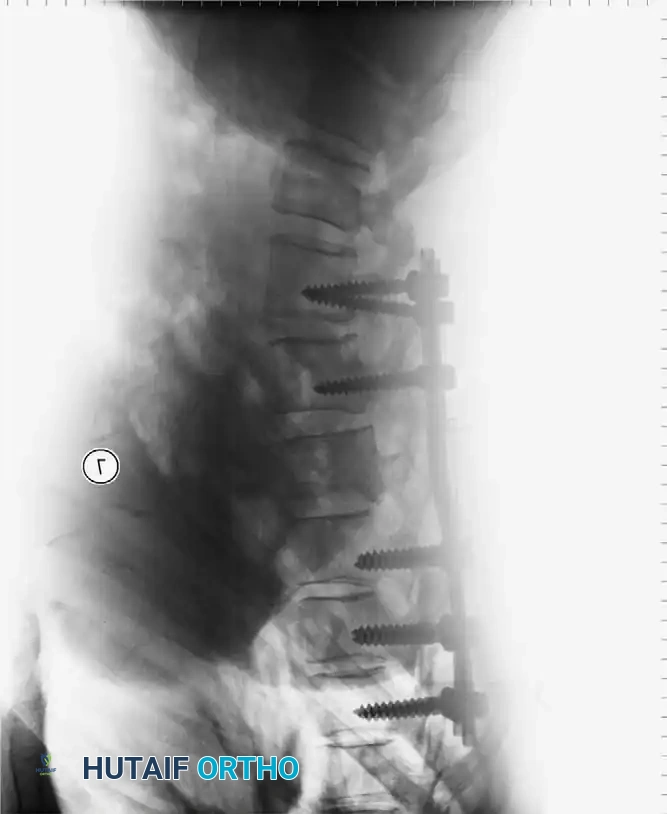

Anterior Plating Technique (Technique 35-16)

When anterior column reconstruction is required (e.g., post-corpectomy), anterior plating provides rigid stabilization.

- Measurement and Selection: Measure the distance between the middle of the cranial vertebra and the middle of the caudal vertebra to be included in the fixation. Use this caliper measurement to select the appropriate plate length.

- Contouring: If necessary, use a plate bender to conform the plate to the patient's specific spinal anatomy. Make several slight bends along the length of the plate and between the screw holes to obtain a consistent radius of curvature.

- Positioning: Using a plate holder, place the plate on the vertebral column in the optimal anatomical position.

- Temporary Fixation: Temporarily fix the plate with small pins screwed into the cortical wall. Insert these self-cutting pins diagonally through the screw holes to obtain sufficient provisional stability.

- Drilling: Place the drill guide on the plate. The guide limits pilot holes to the orientation of the integrated blocking ring (0 to ± 10 degrees sagittally and 6 degrees axially). Use the appropriate drill bit (10 mm, 12 mm, 14 mm, 16 mm, or 18 mm) to prepare the pilot hole.

- Screw Insertion: While tapping is an option, modern screws are typically self-tapping. Insert the 4.0-mm or 4.5-mm screws into the pilot holes. Tighten until locked into the plate, ensuring the locking mechanism (washer) fully covers the screw head.

- Graft Securing: If a corpectomy and structural grafting were performed, secure the graft to the plate using standard 4-mm screws placed in the intermediary screw holes.

- Closure: Thoroughly irrigate the wound and close in layers over a subfascial drain.

Associated Surgical & Radiographic Imaging